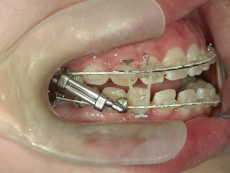

● 臼歯部の後方移動

臼歯を後方に牽引し、移動させることでスペースを確保し歯列を整えます。

臼歯にリンガルアーチという装置を装着し、ミニインプラントを固定源に臼歯を後方に牽引します。

臼歯が後方に下がり、臼歯と小臼歯の間にスペースができました。唇側にワイヤ-をSETし、前歯の歯並びの改善を併行して行います。